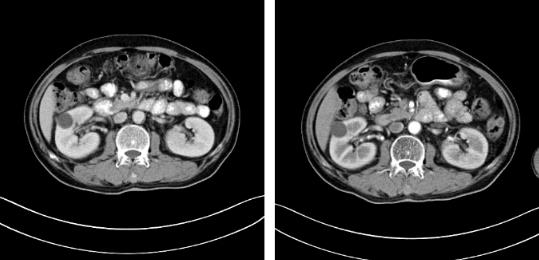

2017年9月29日,从CT影像看到右肾情况更为严重。为减缓肿瘤增长的速度,专家进行商议后,最终决定由牛立志教授主刀为安图叔叔进行了右肾肿瘤冷冻消融术。手术开始后,牛立志教授在CT和超声引导下,同时使用两根冷冻针固定病灶,精准灭活肿瘤;术后很成功无不良反应。术后一周进行第二次双肾肿瘤冷冻消融术。安图叔叔儿子笑道:“当时真的很紧张,医生劝慰我无须担心,都交给他们,我们都很清楚知道父亲的病情,真的很感谢也很庆幸我父亲遇到复大的医护人员,免受开刀之痛。住院期间医护人员很尽心尽力的照顾父亲,手术的成功离不开他们的辛劳付出。”

冷冻治疗手术中

自2017年做冷冻消融术后,安图叔叔两年多时间肿瘤不仅没有增长并多次检查没有复发迹象。安图叔叔认为,冷冻给他带来新的希望,又一次看到复大创造新的奇迹。